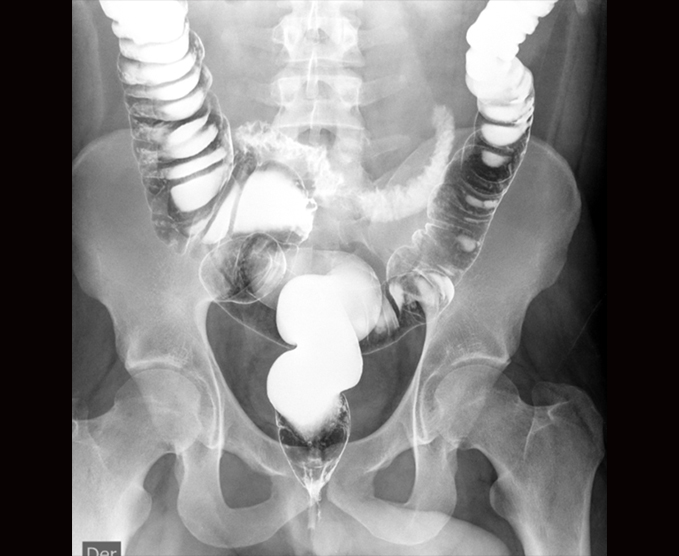

Algunos de nuestros estudios contrastados.

- Cistocrama miccional